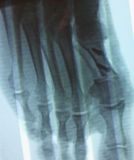

1. Ηallux valgus of the right foot in a 28-year-old female.

Treatment: Scarf osteotomy of the first metatarsal

I. Anteroposterior x-ray foot during procedure shows the scarf osteotomy with two screws II. This image shows the foot in a standing position one year down the line from the procedure. The young lady is very happy.